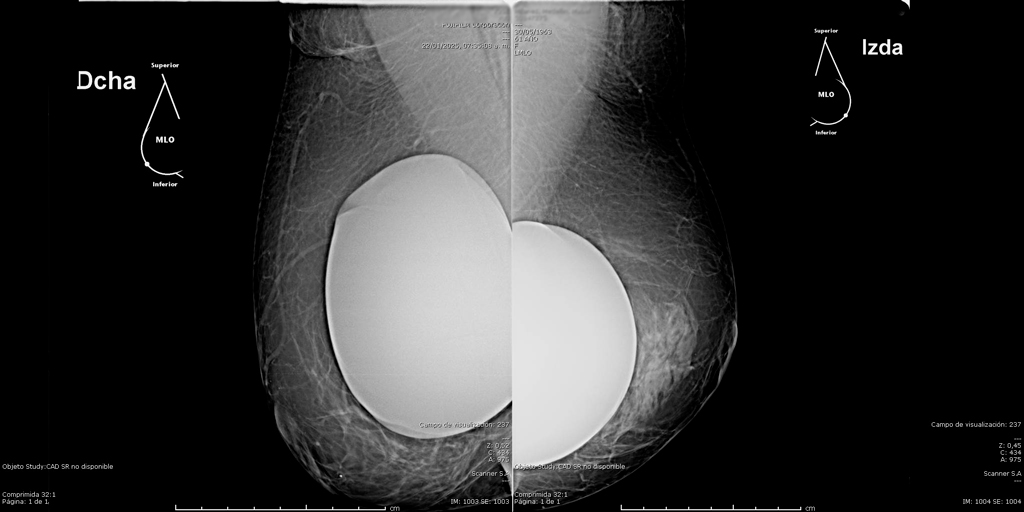

La mamografía es un estudio de diagnóstico por imagen que utiliza bajas dosis de rayos X para obtener imágenes detalladas del tejido mamario. Es una herramienta fundamental para la detección temprana del cáncer de mama y otras patologías mamarias, incluso antes de que sean evidentes al tacto o generen síntomas. Su uso regular en controles preventivos permite salvar vidas al facilitar diagnósticos oportunos y tratamientos más efectivos.

En SCANNER S.A, nuestros equipos digitalizados permiten detectar cambios mínimos en el tejido mamario con alta claridad, permitiendo asi tener un diagnostico preciso y entregar unos resultados reales a nuestros pacientes.